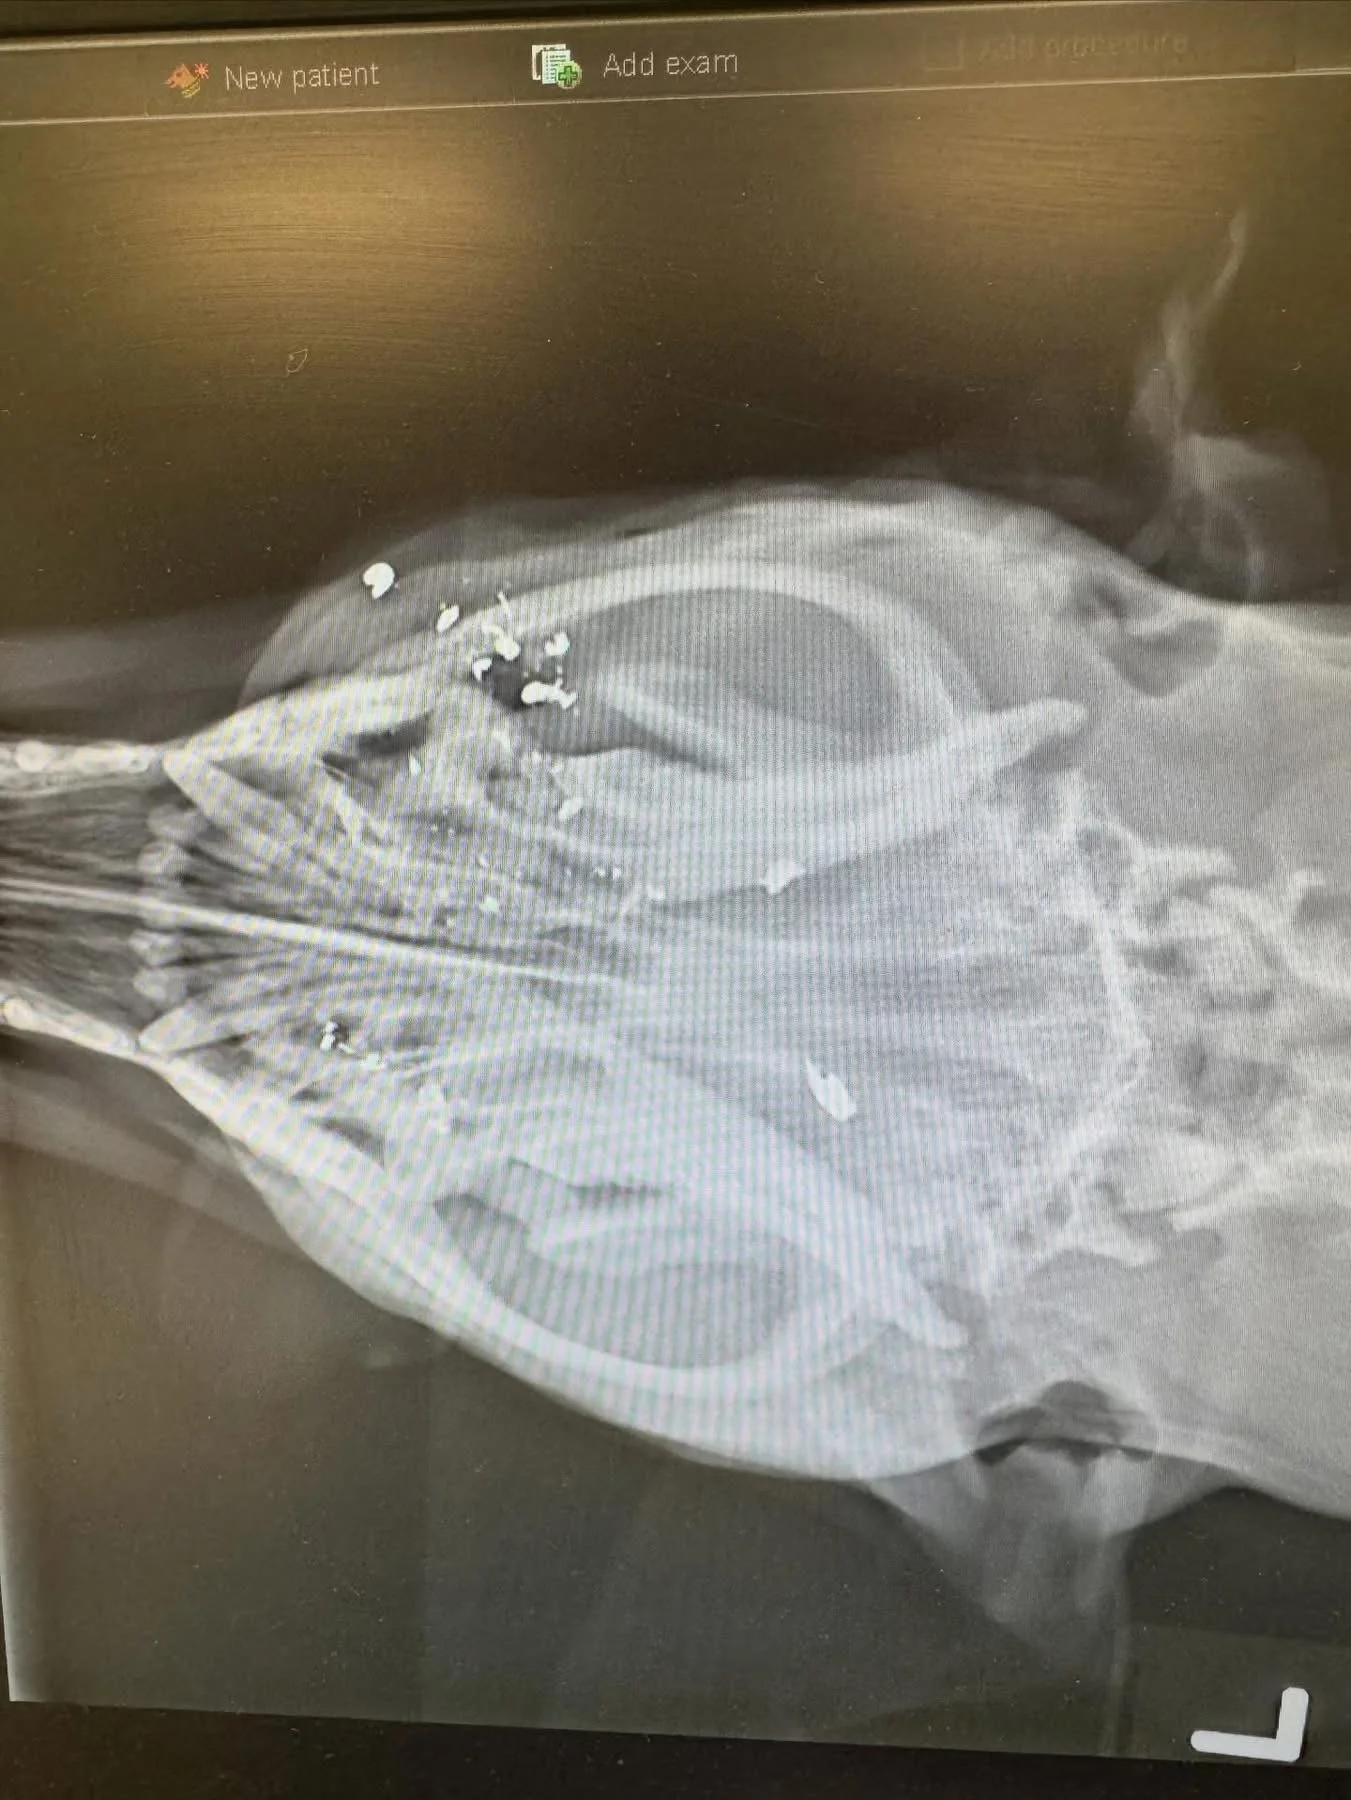

We finally got her safely into my car and dropped her off at the vet. The bullet had gone right through her cheek, tongue, and into her brain. Unfortunately, there’s not much we can do except strong pain medication, antibiotics, and hope 🙏 for a positive outcome.